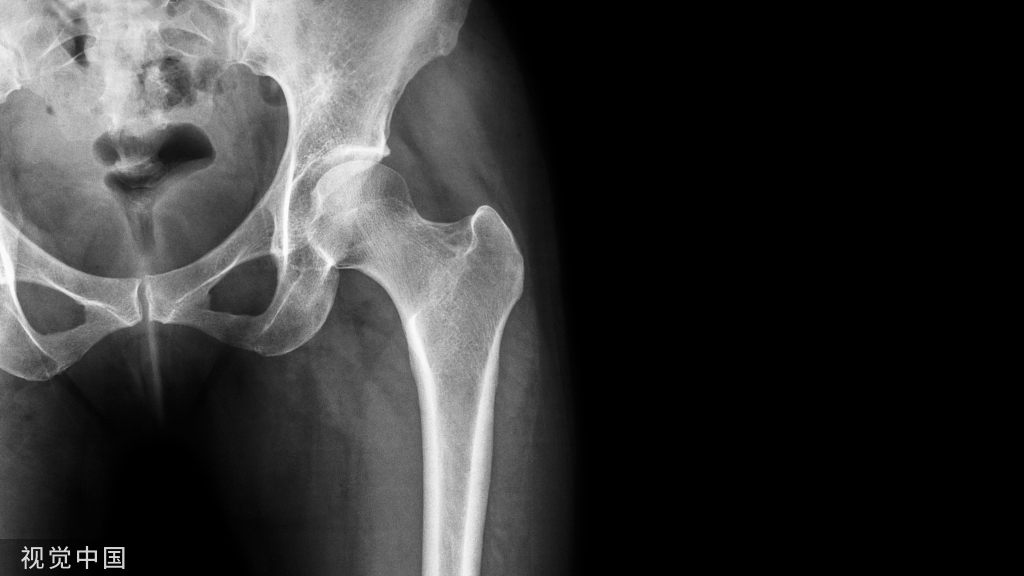

11圆点征

圆点征(Polka-dot sign)

圆点征指的是在横断面图像上,椎体骨松质呈粗大网眼状改变,残留骨小梁增粗呈稀疏排列的多发粗点状高密度影。此征象多提示脊柱血管瘤。

典型病例

胸椎血管瘤。A.CT 横轴位骨窗示椎体右侧部骨小梁稀疏粗大,呈圆点征;B. 矢状位 MPR 图像呈现栅栏征。